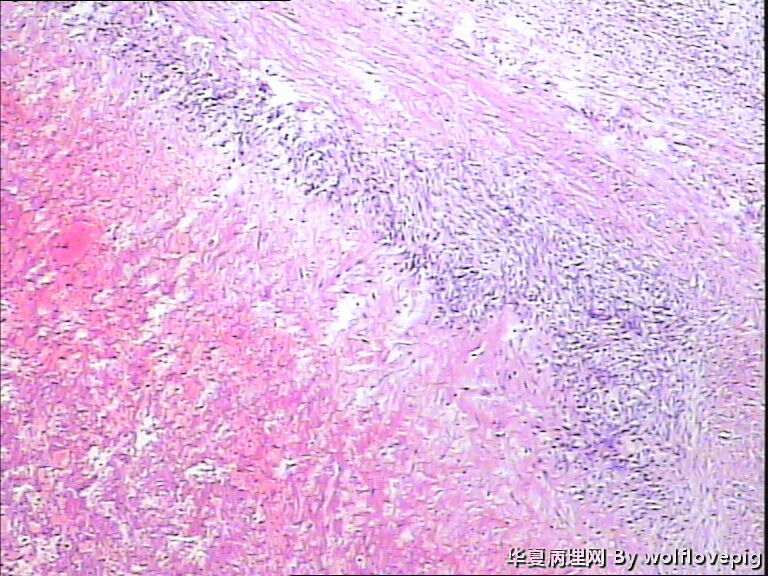

37y,肌壁间可见多个小结节0.2~0.8cm。